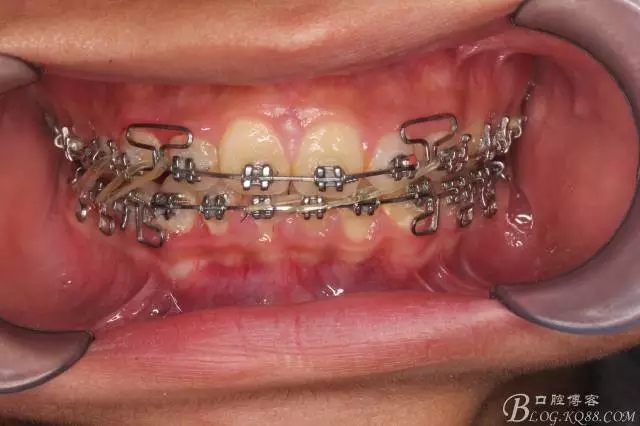

佩戴三個月的FR2, 效果奇佳!前牙基本達到淺覆蓋,淺覆合!接下來進入二期直絲弓固定正畸,排齊階段!

接下來盡管配合些雙側(cè)后牙對角牽引,咬合關(guān)系依,不盡人意。